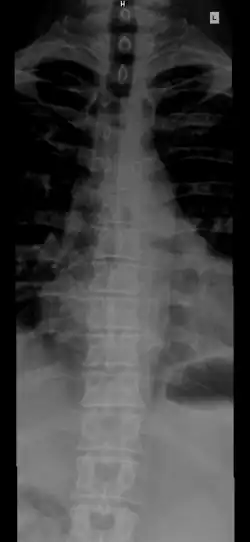

![]() The human spinal column and its regions | |

The spinal column, also known as the vertebral column, spine or backbone, is the core part of the axial skeleton in vertebrates. The vertebral column is the defining and eponymous characteristic of the vertebrate. The spinal column is a segmented column of vertebrae that surrounds and protects the spinal cord. The vertebrae are separated by intervertebral discs in a series of cartilaginous joints.[1] The dorsal portion of the spinal column houses the spinal canal, an elongated cavity formed by the alignment of the vertebral neural arches that encloses and protects the spinal cord, with spinal nerves exiting via the intervertebral foramina to innervate each body segment.

The vertebrae in the human vertebral column is divided into different body regions, which correspond to the curvatures of the vertebral column. The articulating vertebrae are named according to their region of the spine. Vertebrae in these regions are essentially alike, with minor variation. These regions are called the cervical spine, thoracic spine, lumbar spine, sacrum, and coccyx. There are seven cervical vertebrae, twelve thoracic vertebrae, and five lumbar vertebrae.

From top to bottom, the vertebrae are:

- Cervical spine (neck): 7 vertebrae (C1–C7)

- Thoracic spine (chest/upper back): 12 vertebrae (T1–T12)

- Lumbar spine (lower back): 5 vertebrae (L1–L5)

- Sacrum (pelvis region): 5 (fused) vertebrae (S1–S5)

- Coccyx (tailbone): 4 (3–5, fused) vertebrae